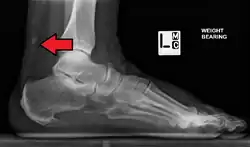

Calcification from dermatomyositis

X-Ray of the knee in a person with dermatomyositis.

Magnetic resonance imaging may be useful to guide muscle biopsy and to investigate involvement of internal organs;[21] X-ray may be used to investigate joint involvement and calcifications.[22]